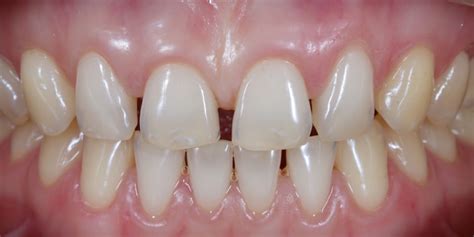

Si se produce un desequilibrio, por ejemplo un incremento de la presión de la lengua debido a una posición de reposo patológica o una disfunción deglutoria, los círculos funcionales exterior e interior se desequilibran.

Fig. 17. Como consecuencia de la posición de reposo patológica de la lengua surgió una protrusión con grandes espacios interdentales y mordida cruzada frontal, a vista oclusal y b frontal.

Dado que las medidas logopédicas no condujeron al éxito, se utilizó un aparato que fue dado a conocer en Alemania especialmente por el ortodoncista estadounidense Douglas Toll. El aparato consiste en última instancia en un arco lingual modificado, y también es conocido cariñosamente como «reeducador lingual». El objetivo del aparato es, mediante la aplicación selectiva de estímulos dolorosos, apartar la lengua de su posición patológica y guiarla hacia la posición correcta.